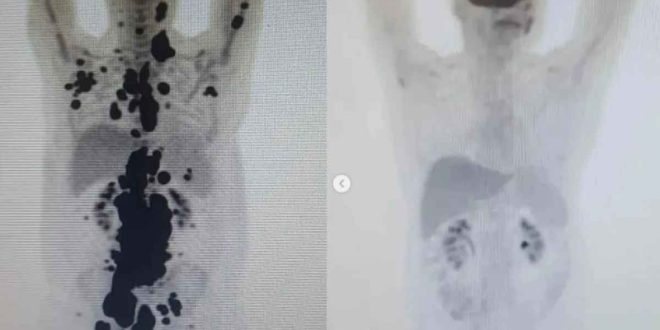

Las imágenes del antes y después de la terapia que Paulo compartió en sus redes sociales y muestran cómo el cáncer desapareció por completo devolviéndole la salud al hombre.

Tras someterse y lograr resultados impresionantes, se difundieron las imágenes del antes y después de la terapia a través de una tomografía computarizada que Paulo compartió en sus redes sociales y muestran cómo el cáncer desapareció por completo devolviéndole la salud al hombre.

“En abril de 2018 estaba en quimioterapia. Era mi segundo cáncer y mi primer linfoma; no tenía idea de que habría dos más por venir. Fueron 1.800 días, decenas de sesiones de quimioterapia y pruebas de imagen, hospitalizaciones, trasplantes de médula ósea, cuatro biopsias, covid, sangrados, UCI… Incluso, los médicos consideraron un milagro que saliera vivo de la hospitalización y la cirugía. Ahora, en 2023, las imágenes del antes y después no dejan lugar a dudas: ¡Remisión completa de mi tercer linfoma! Es el éxito de Cart T Cell”, escribió en sus rede sociales.